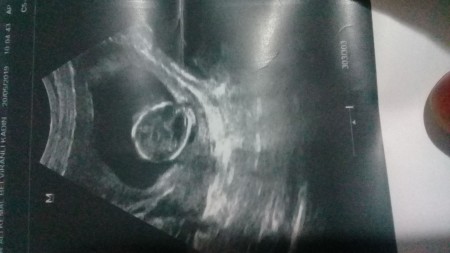

image

bebğim hareketi ancak başladı bu ultrason fotoğrafı 16.5 haftalıkken çekilmişti şu an 18.1 haftalık hamileym

Gebelik haftası 16.5 günlük

Yanlış görmüyorsam baş çevresini çekmiş doktor sanki kafasının tepesi

Canım doktor burda kafasının resmini çekmiş başka resim vermedi mi

Tek  kafasının resmini vermesi tuhaf ben devlete gidiyorum doktorum 4 tane resim veriyor her halini doktordan doktora değişiyor